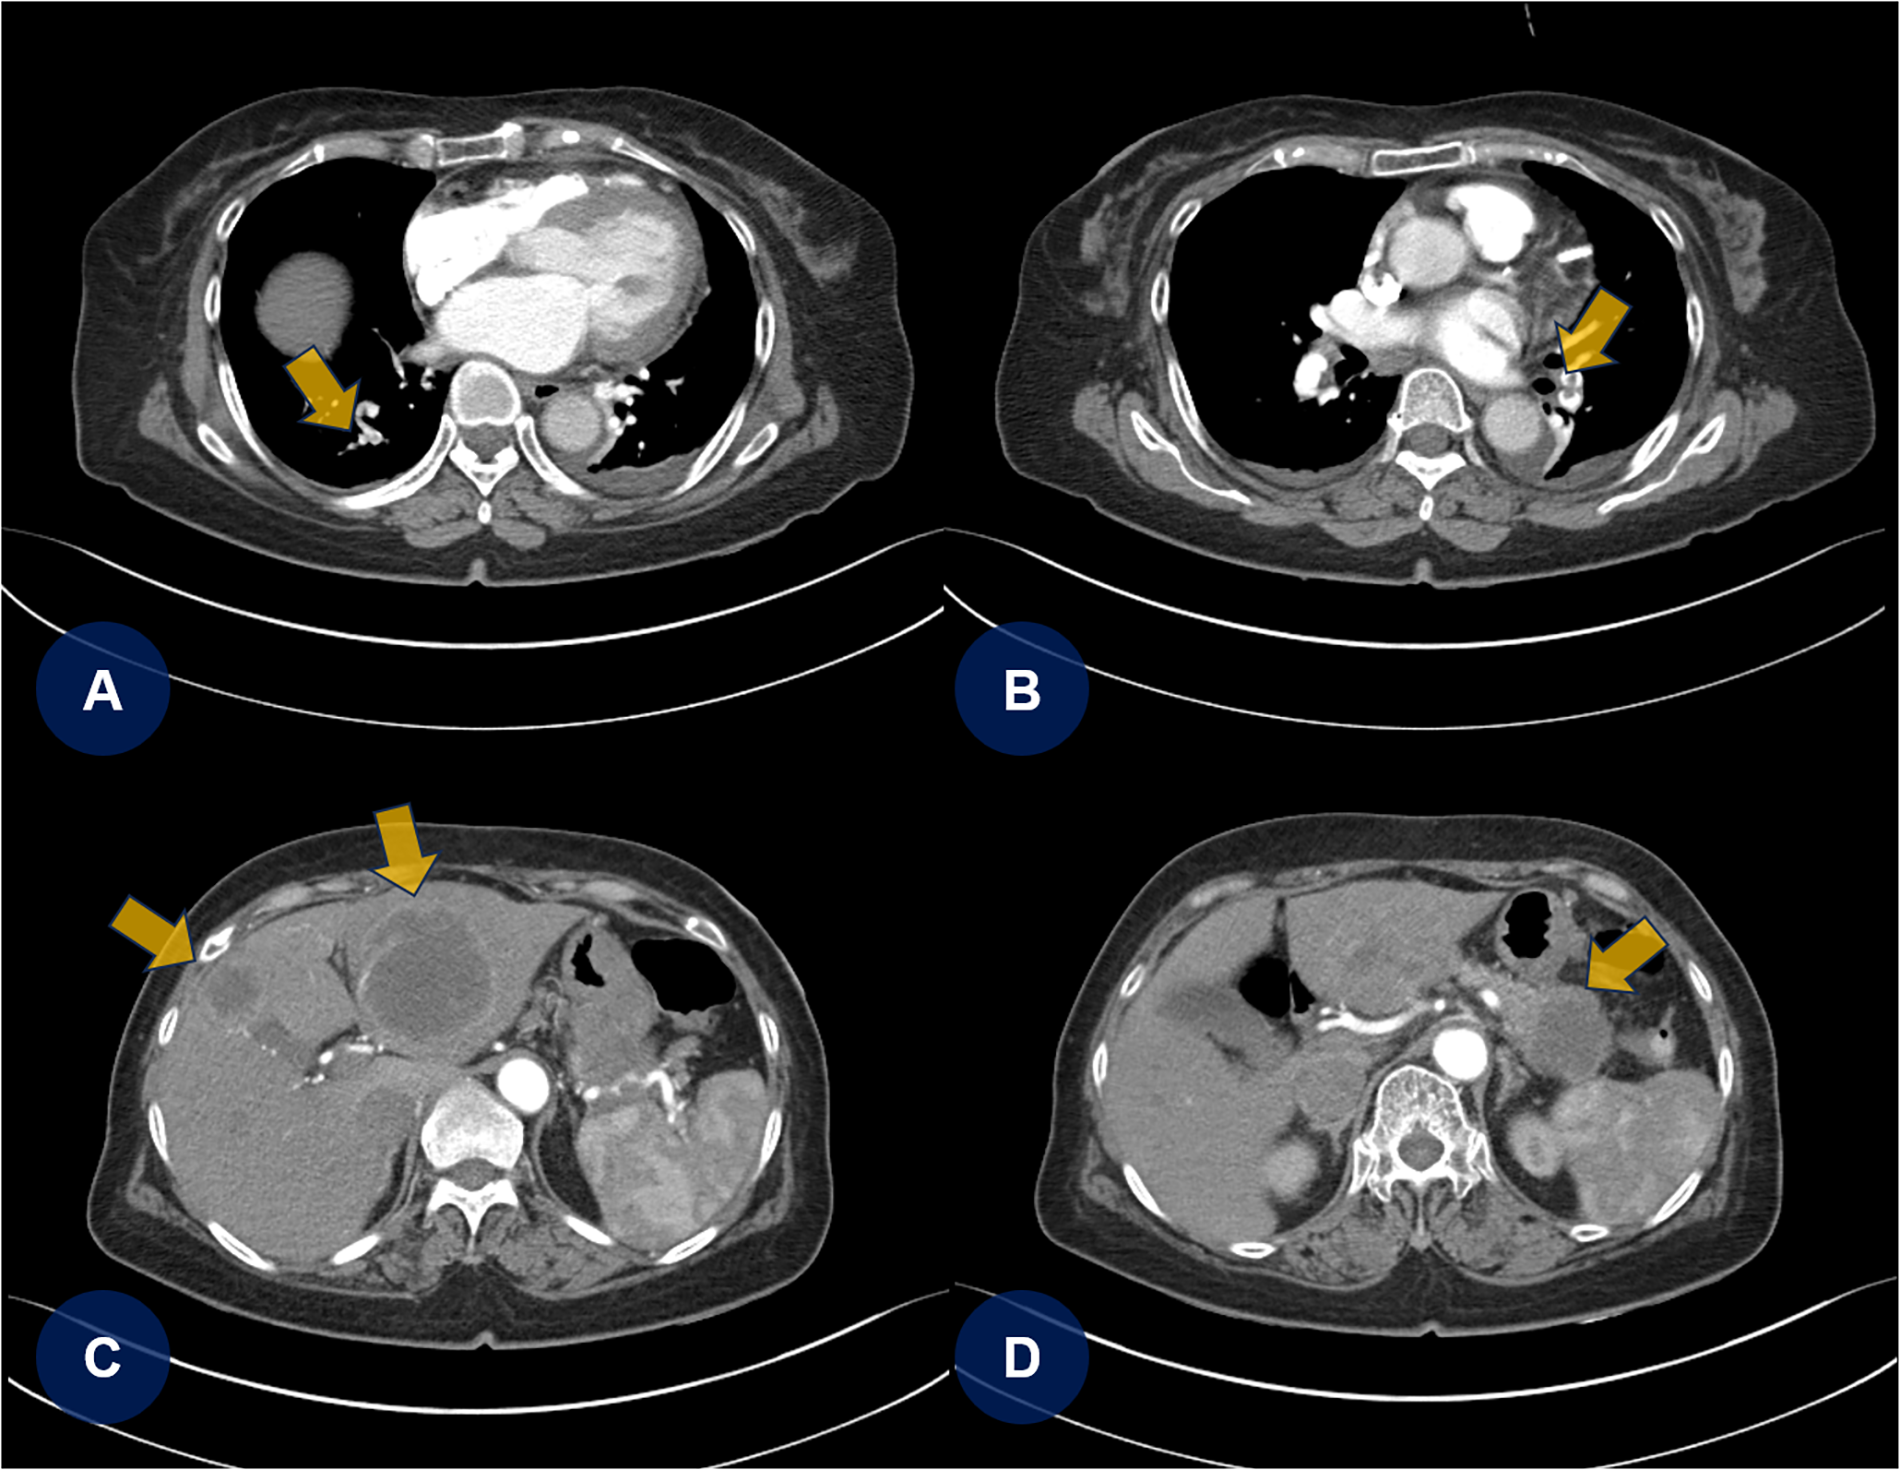

A few days later, the patient experienced recurrent abdominal discomfort accompanied by intermittent episodes of mild fever. SARS-CoV-2 and influenza rapid antigen test results were negative. The treating physician decided to perform chest and abdominal computed tomography angiography (CTA) to identify potential underlying abnormalities, including inflammation, infection, thromboembolic lesions, or malignancies. CTA revealed PTEs (Figures 2A,B, yellow arrows) and multifocal round hepatic lesions along with a solitary mass-like lesion in the pancreatic tail (Figures 2C,D, yellow arrows), suggestive of primary pancreatic cancer. Additional venous CTA confirmed the presence of deep vein thrombosis (DVT) in both popliteal veins (Supplementary Figure S2). To manage the PTE and DVT, intravenous heparin was initiated. One week later, the heparin therapy was transitioned to a direct oral anticoagulant (DOAC), apixaban (5 mg twice daily). Dynamic contrast-enhanced magnetic resonance imaging subsequently confirmed the diagnosis of primary pancreatic cancer with hepatic metastasis (Figures 3A,B, yellow arrows).

Figure 2

Chest and abdominal CTA. (A,B) Chest CTA reveals multifocal pulmonary thromboembolisms (yellow arrows). (C,D) Abdominal CTA shows multifocal round-shaped hepatic lesions with a solitary mass-like lesion in the tail of the pancreas. CTA, computed tomography angiography; PTE, pulmonary thromboembolism.